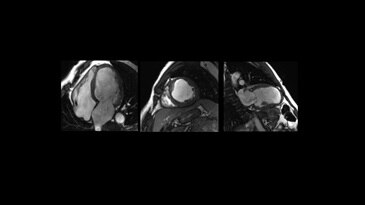

With our intuitive cardiac techniques, you can assess morphology, flow, function and tissue viability plus gain crucial insights into vascular structure and flow dynamics. CVWorks provides the flexibility to adapt to different patient types with exams that vastly simplify workflow.

With CVWorks, multi breath-hold imaging can be a thing of the past. Our latest Single shot MDE and Black Blood techniques provide patient-friendly alternatives to uncomfortable breath-holds.

With our workflow-simplified QuickStep protocols, scanning whole body vasculature can be done in less than 6 minutes. High performance gradients allow bright blood pool and myocardial tissue contrast on Cine FIESTA while preserving spatial resolution.NeuroWorks

2D Cine FIESTA

Black Blood - SSFSE

PS MDE